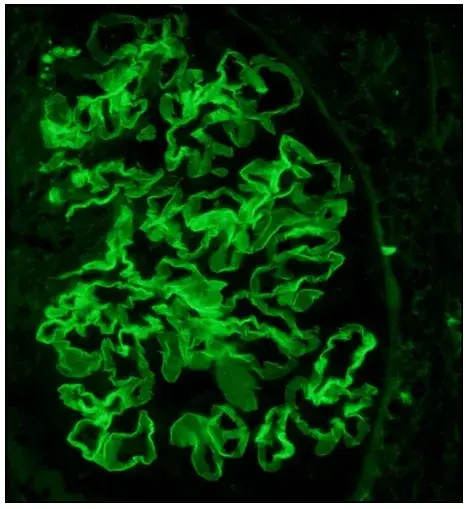

Biopsia de pele revelou cristais de colesterol obstruído arteríolas.